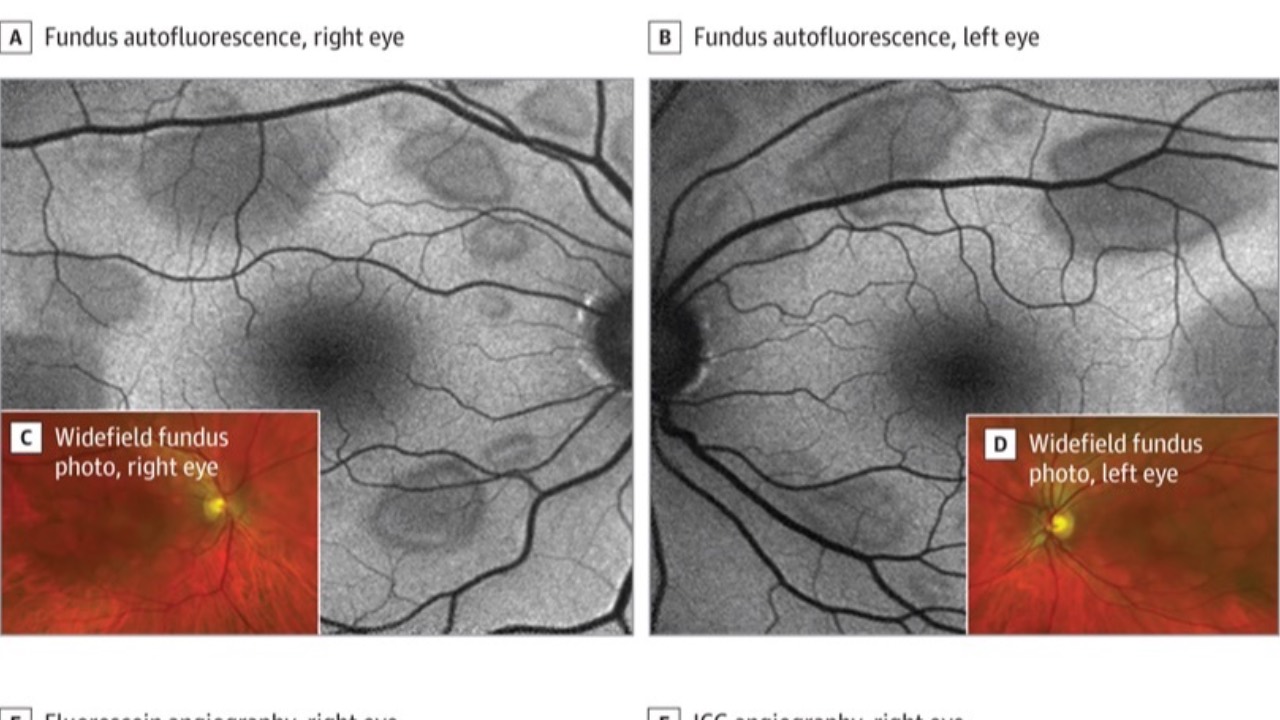

Hair Dye Retinopathy

Retinopathy associated with hair dye aromatic amines (RAHDAA) may be an emerging concern. This condition manifests as multiple bilateral serous retinal detachments, mimicking MEK inhibitor-associated retinopathy.

Symptoms are typically following exposure to hair dyes containing aromatic amines. ...